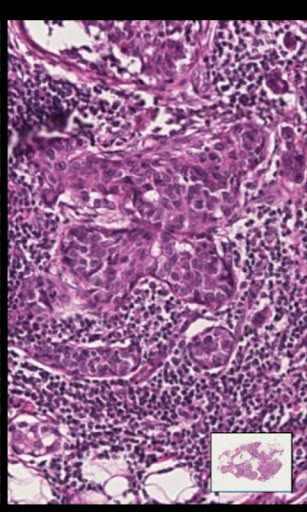

This application allows for a remote pathologist to review and navigate high quality images of diagnostic quality using either the cellular network or WIFI networks on the Android device. Using the application rapid specialist referrals can be made, without access to a computer, a microscope or the original specimen. The pathology image can be reviewed by the pathologist and used to provide a diagnosis used in cancer and other disease treatments.